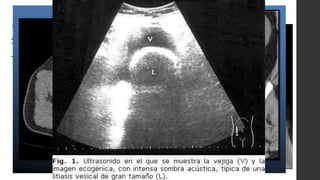

Litiasis

Vesical: